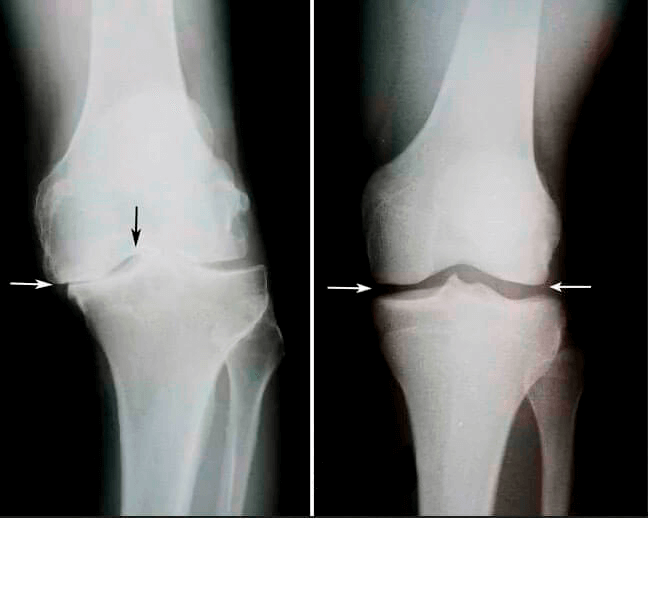

Tavsiye için bana döndü, 1.5 ay sürdüğü söylenen Percutane ve servikal omurganın ikinci bir röntgeni için reçete edilen röntgene baktım.